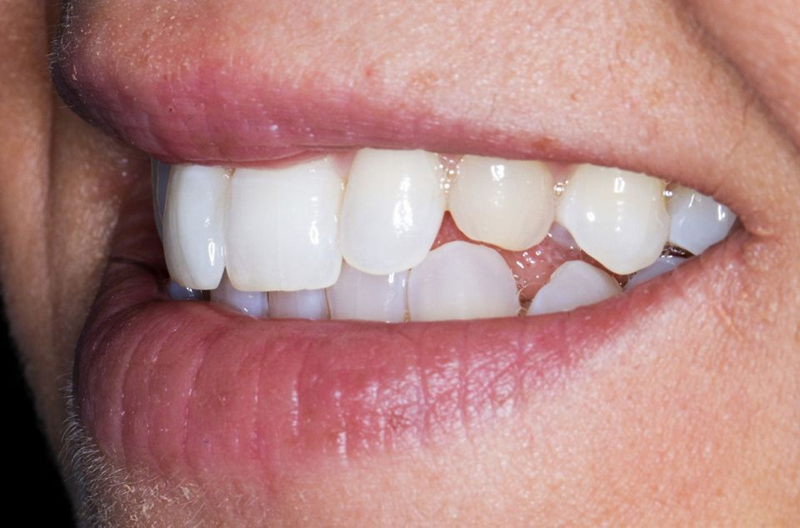

口外检查中,面部评价显示面部对称、比例匀称。微笑分析显示中线矢状面与微笑中线重合,上切牙和尖牙的暴露率为90%(图1)。微笑还显示侧切牙形状不同,与对侧恒尖牙相比,左上乳尖牙更短、更窄、颜色更黄(图2-4)。

Fig. 4: Left lateral view of the patient’s smile.